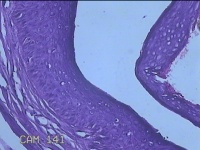

左眼外侧缘上肿物

性别

女

年龄

60岁

临床诊断

痣;疣

左眼上睑缘白色丘疹1年余。

灰白粉红色肿物0.8x0.3x0.2cm两个,表面光滑。